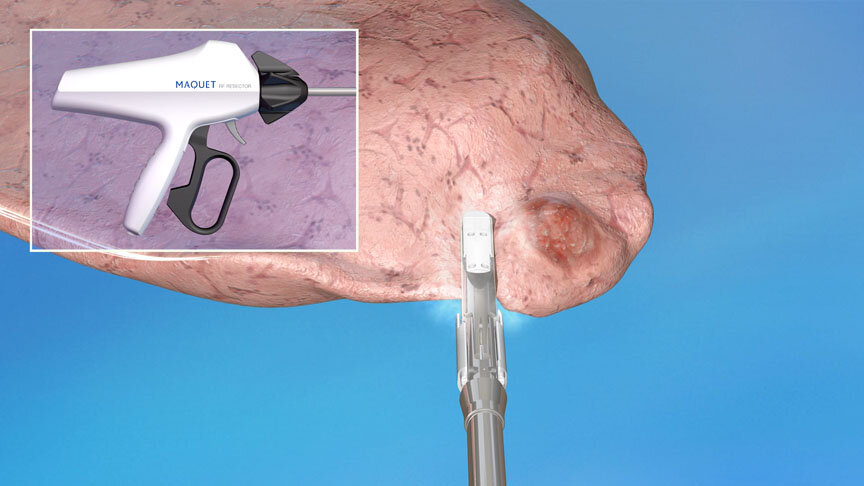

EnCompass F2 Device for cerebral embolic protection system in TAVR procedures

EnCompass Technologies

EnCompass’ F2 filter has pores small enough to block most emboli to the brain while preserving blood flow. During the TAVR procedure, 360-degree wall apposition of the filter in the aortic arch prevents migration. The filter, attached to a self-expanding, nitinol stent, is easy to insert, deploy and retrieve, according to the company. Copyright ©2021 KO Studios.